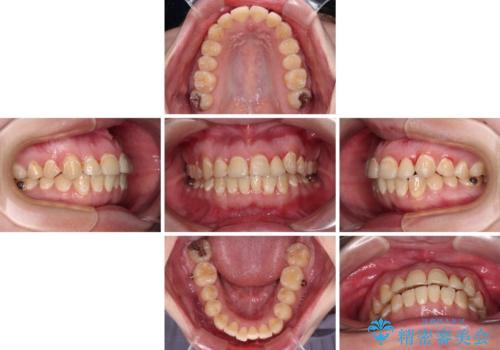

- 前歯のデコボコとクロスバイトが気になり、インビザラインによる矯正治療を希望して来院された患者様です。

上顎側切歯(上の真ん中から2番目の歯)が舌側転位している場合、無理して動かそうとすると歯髄壊死を起こすリスクが高い印象があります。

インビザライン単体でも治療は可能ですが、安全策としてインビザラインで歯列を移動する前に上顎前歯をワイヤー矯正で整え、その後上下歯列をインビザラインにて矯正治療を行うこととしました。

舌側転位している側切歯特有の、切縁の位置が不揃いであったり、根元が内側に引っ込んだ状態であったりという、インビザライン独特の仕上がりになることなく、きれいに整った歯列とすることができました。